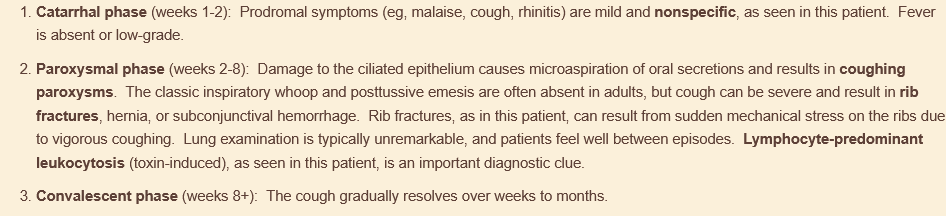

pertussis. look for stepwise illness!